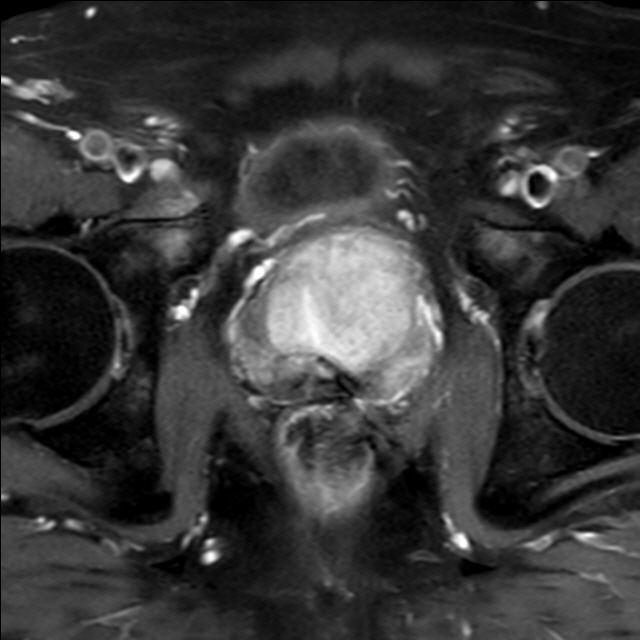

Prostata (mpMRT)

Die multiparametrische MRT der Prostata (mpMRT) bietet eine gute Möglichkeit, mittels bildgebender Diagnostik die Lokalisation, die Ausdehnung und eventuelle Aussaat eines Prostata-Karzinoms darzustellen.

Bei fehlender Darstellung des Tumors im Ultraschall oder vergeblichen Biopsien kann die MRT als Problemlöser eingesetzt werden: Sie zeigt dem Urologen, wo eine weitere Biopsie die Diagnose sichern kann. Außerdem kann die MRT bei sehr ausgedehnten Tumoren einen Überblick über die Beteiligung der Nachbarorgane verschaffen und Absiedlungen (Metastasen) entdecken.